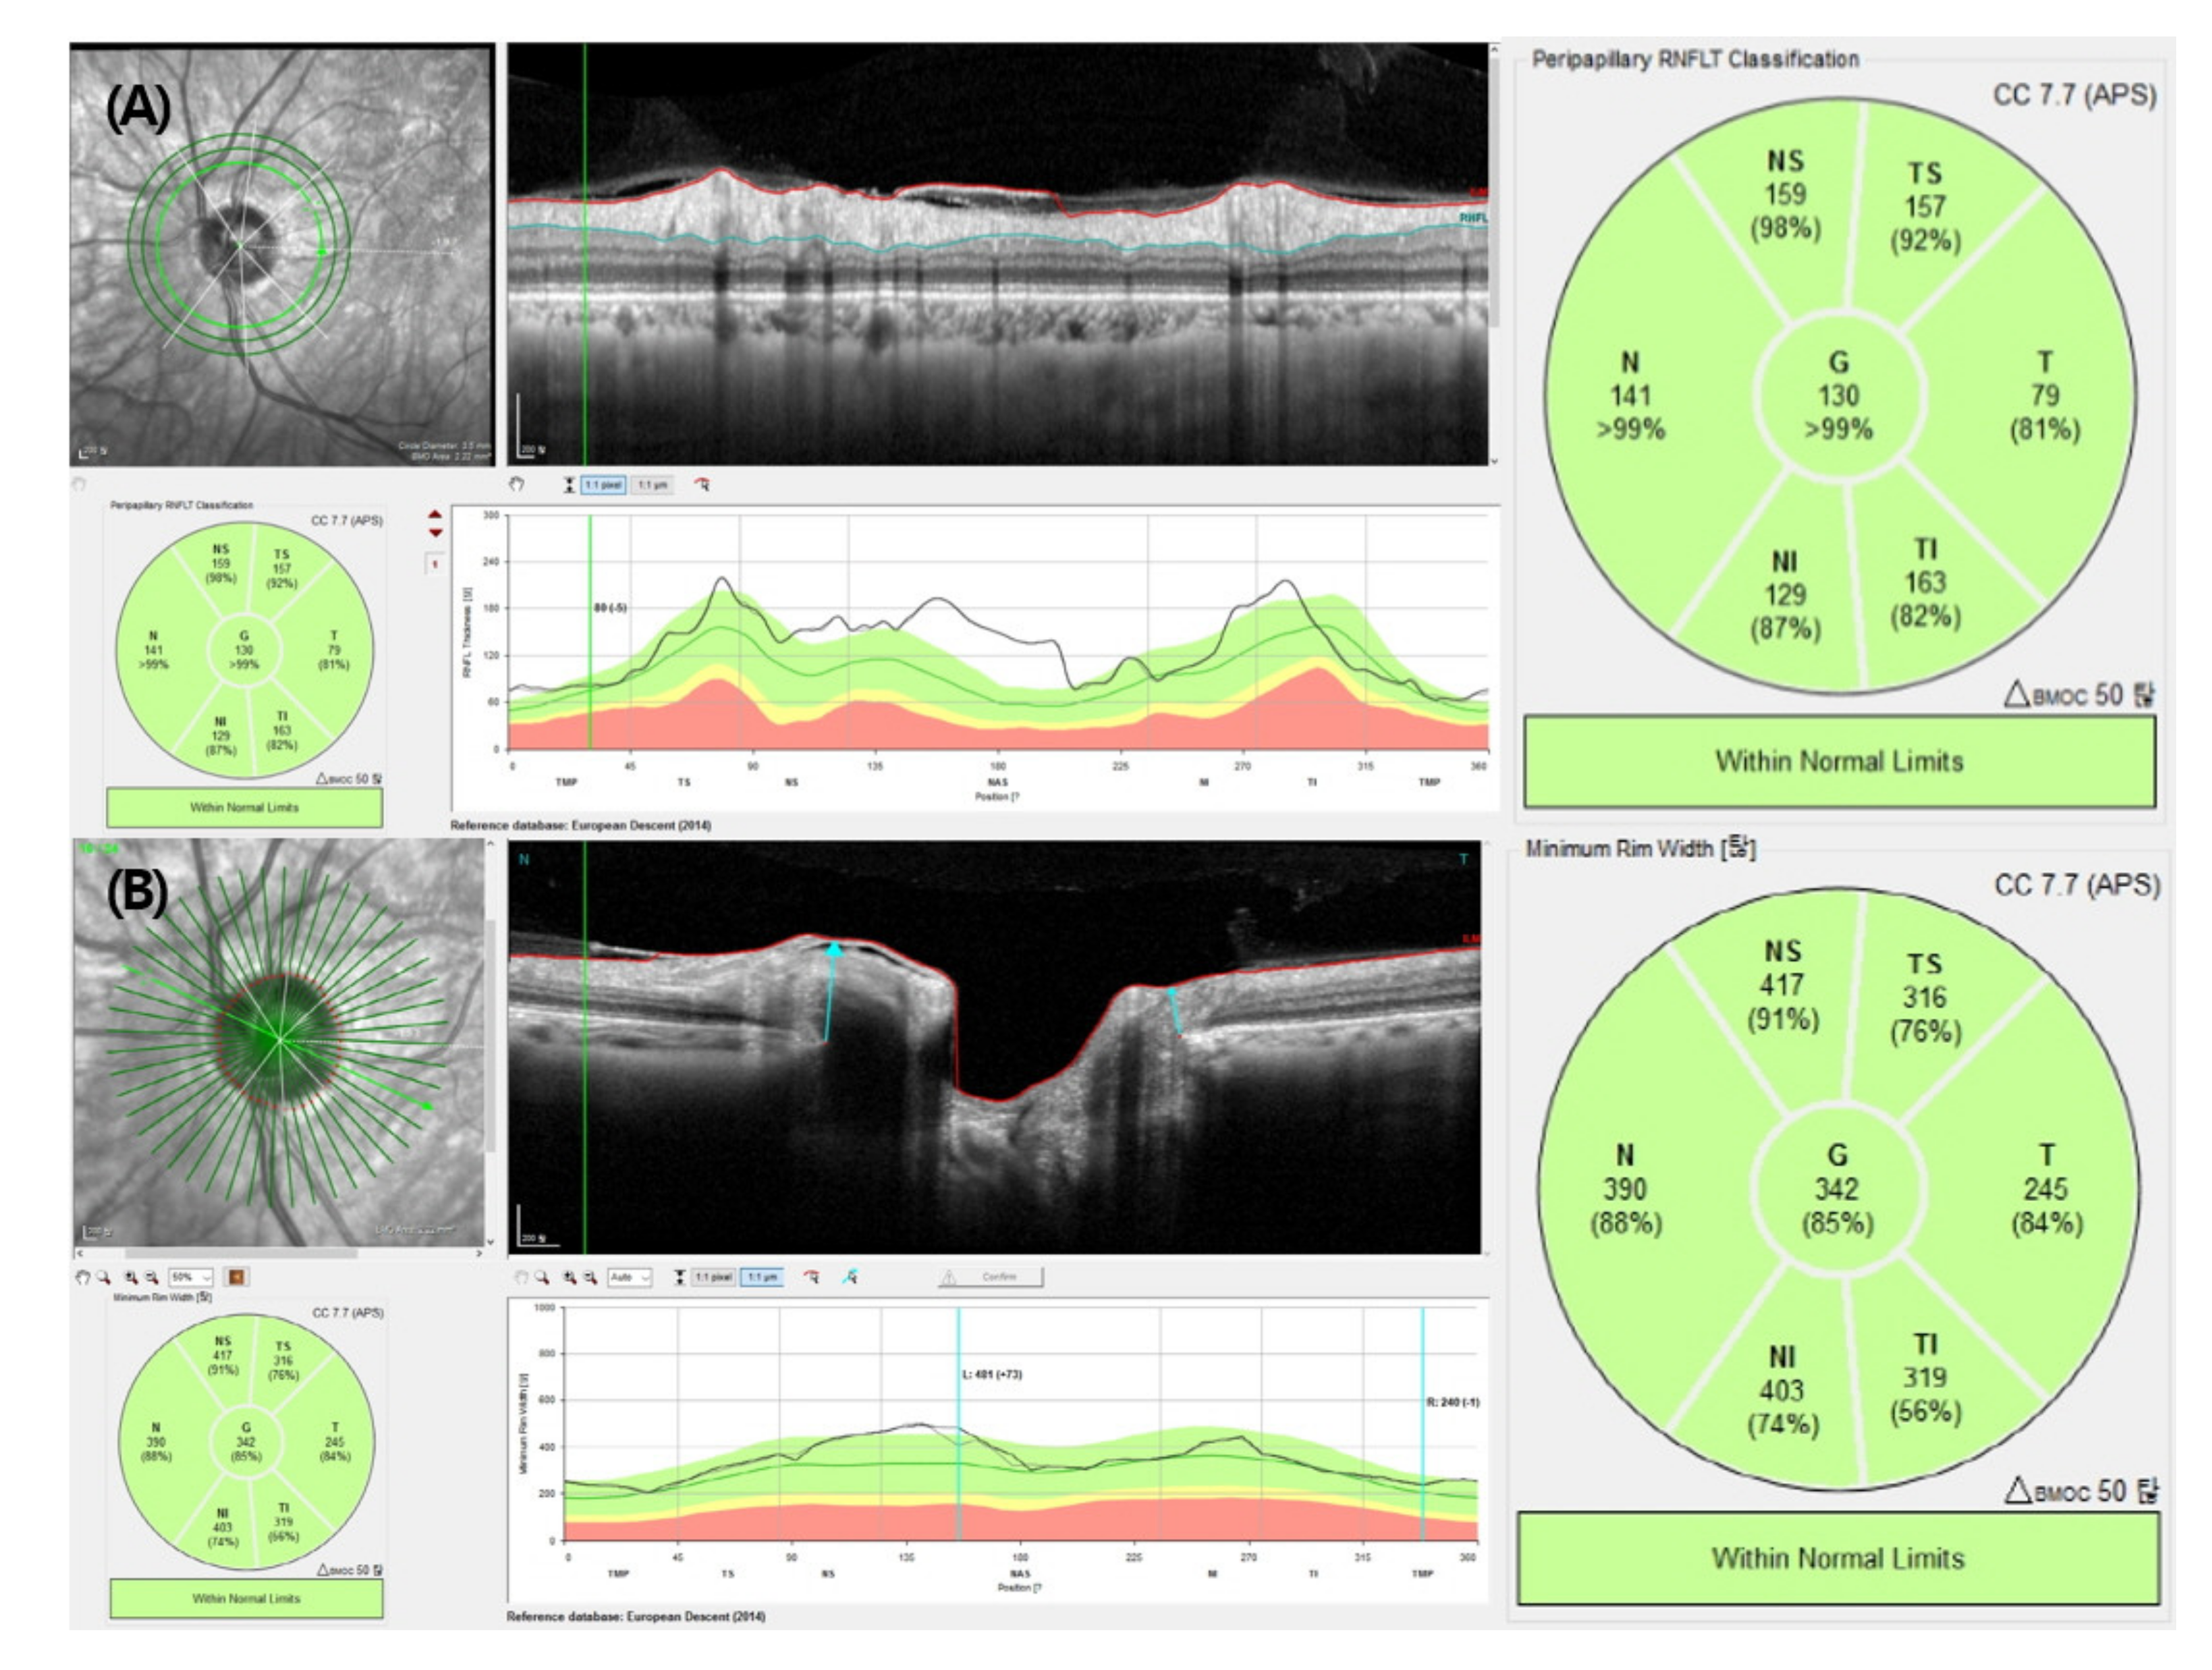

3.2. Average and Sectoral BMO-MRW and RNFL Thickness